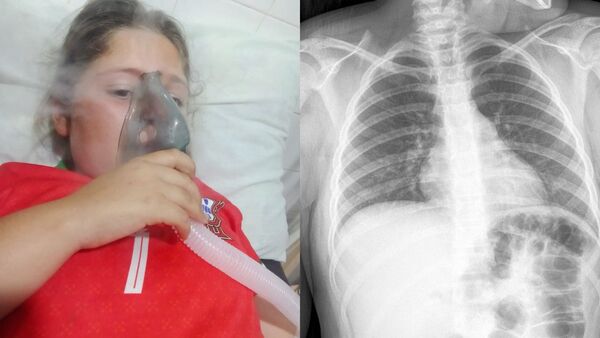

Piden ayuda para niña con epilepsia y problemas pulmonares

La familia Valenzuela, de General Delgado, busca reunir fondos para costear el tratamiento de su hija, cuyo cuadro de salud se agravó en las últimas semanas. ...[Leer más]